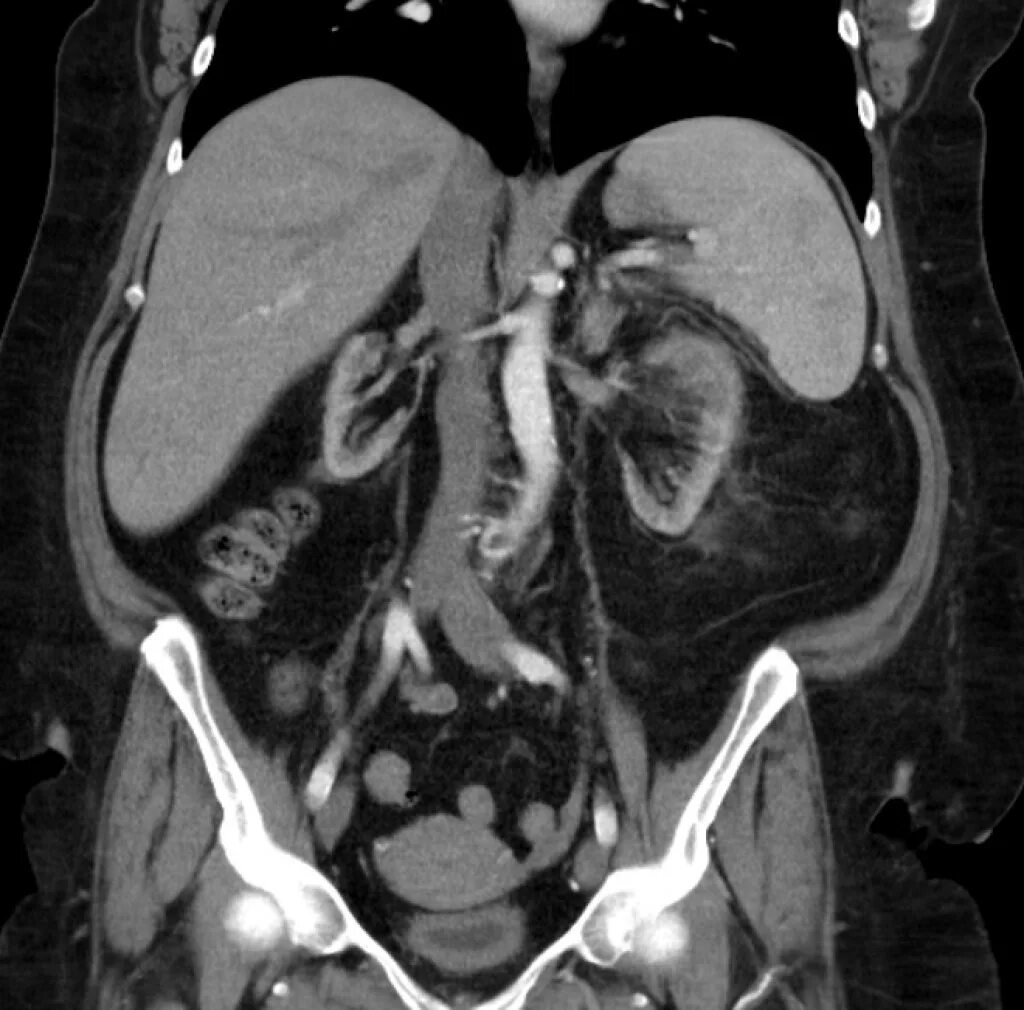

Пиелонефрит кт